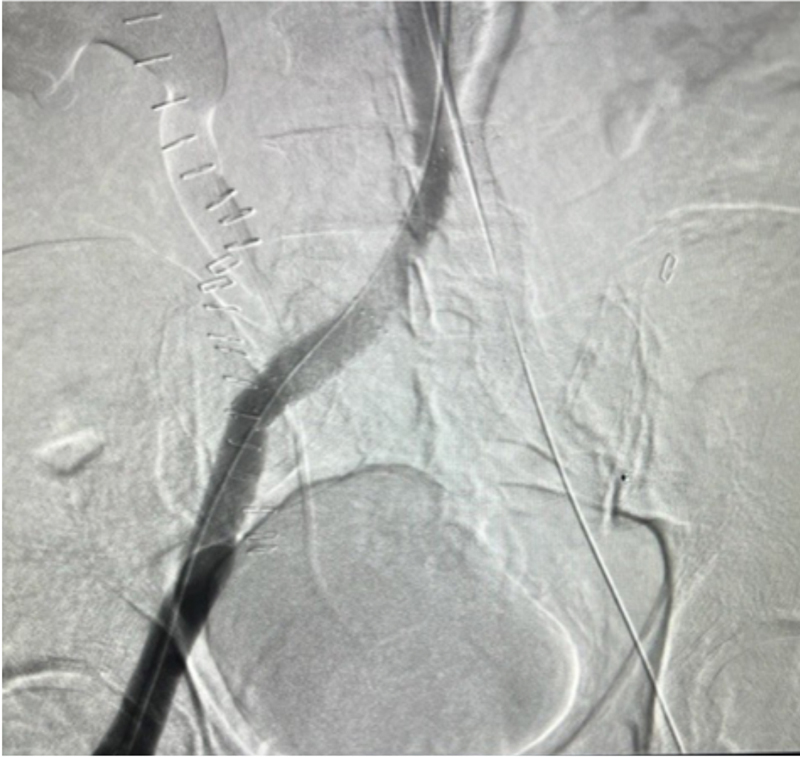

During the mechanical thrombectomy, the patient was placed in the prone position. Bilateral popliteal veins were accessed under ultrasound. Venogram confirmed extensive thrombus in the right and left iliac veins, as well as in the IVC (Figures 1 and 2). Due to IVC involvement, extra-large discs were deployed from the left popliteal vein and above the IVC thrombus for embolic protection. A 13Fr clot retrieving device was inserted on the right. Six passes were made with the clot retriever basket, removing all available IVC and right sided thromboses, which were sub-acute and chronic (Figure 3). The 13Fr clot retriever sheath was then moved to the left popliteal, where five passes were made removing the left-sided thrombi, which also were found to be extremely compacted and likely chronic (Figure 4). The complete thromboses removed are pictured in Figure 5. The patient then received bilateral stents and flow was restored. The patient was discharged two days later on anticoagulation with significant improvement of the lower extremity and pelvic edema.

Figure 1

Figure 1. Left external iliac vein pre-thrombectomy venogram.